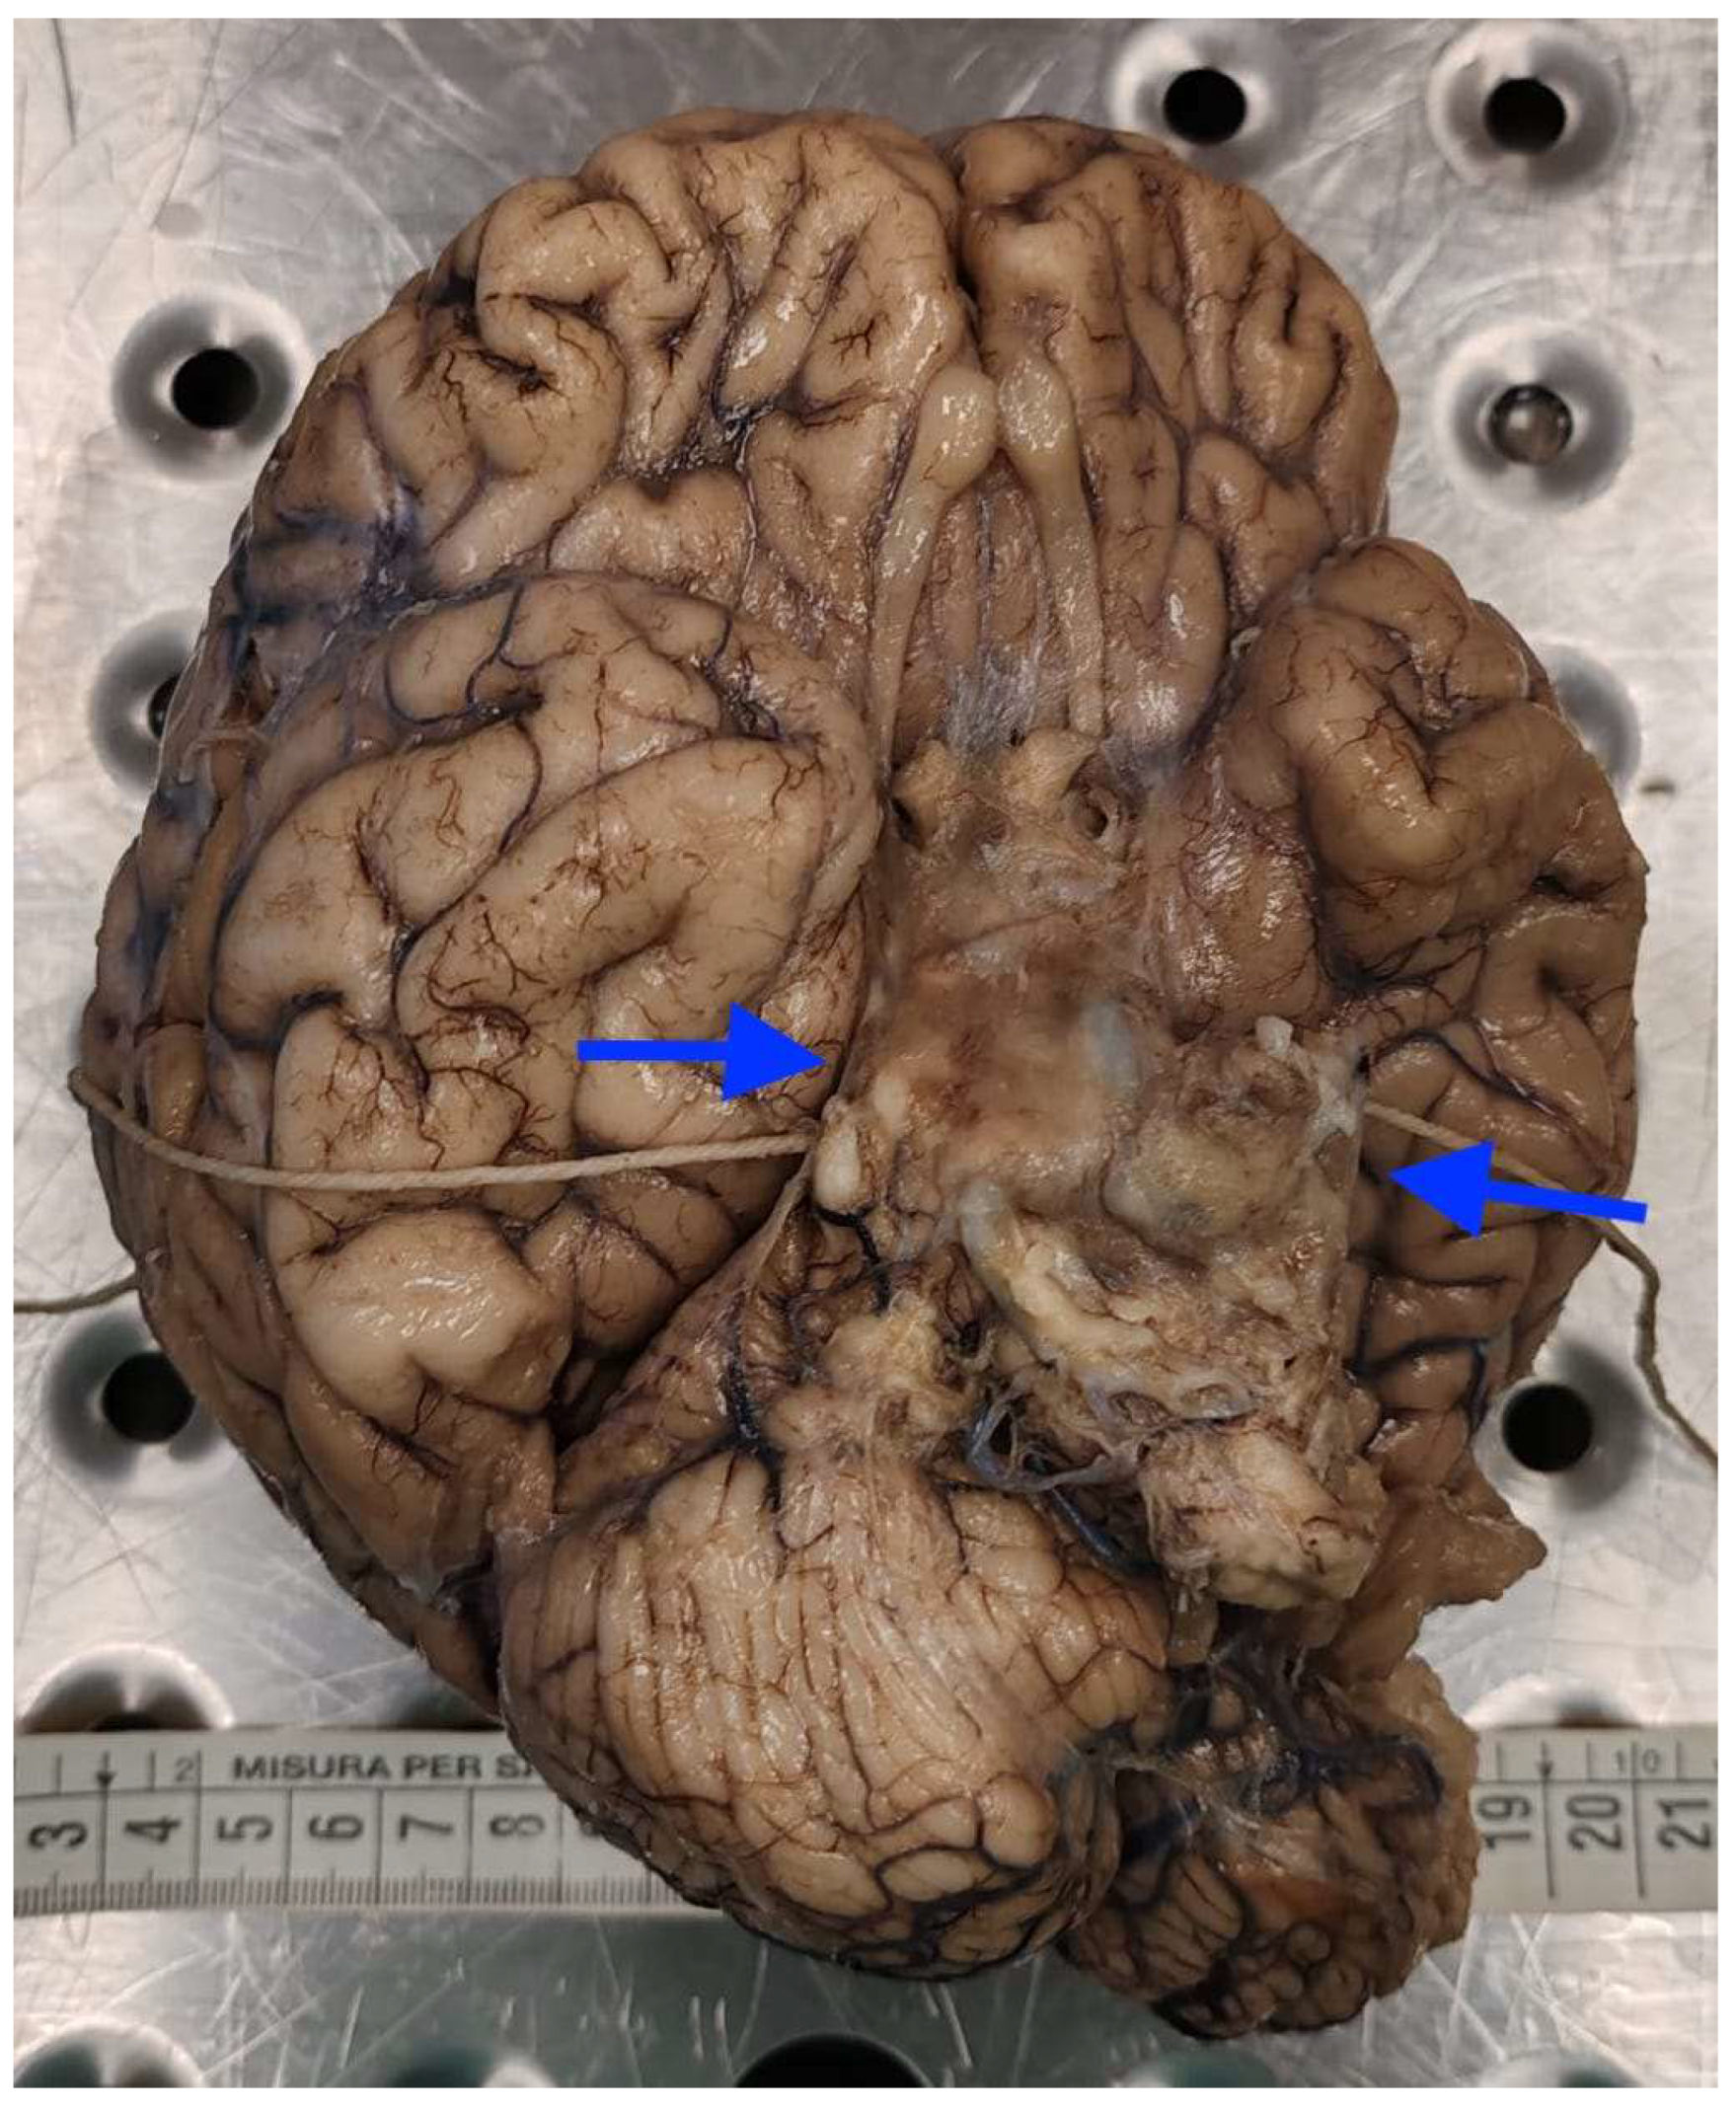

2.1. Autopsy Findings

| ~3 months after surgery | Progressive neurological decline, coma, death | Autopsy: PAS-D and GMS stains positive for fungal elements (Candida albicans) | – | Supportive intensive care until death |